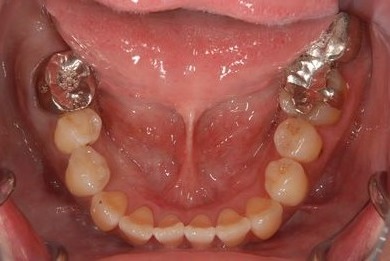

治療前

• 治療前